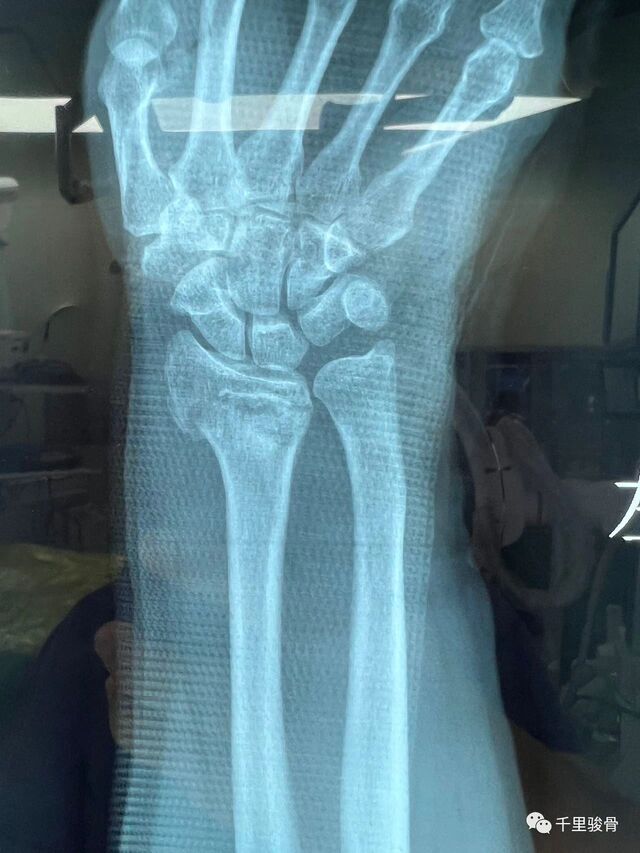

麻醉下透视复位

微信图片_20240102194812.jpg

微信图片_20240102194819.jpg